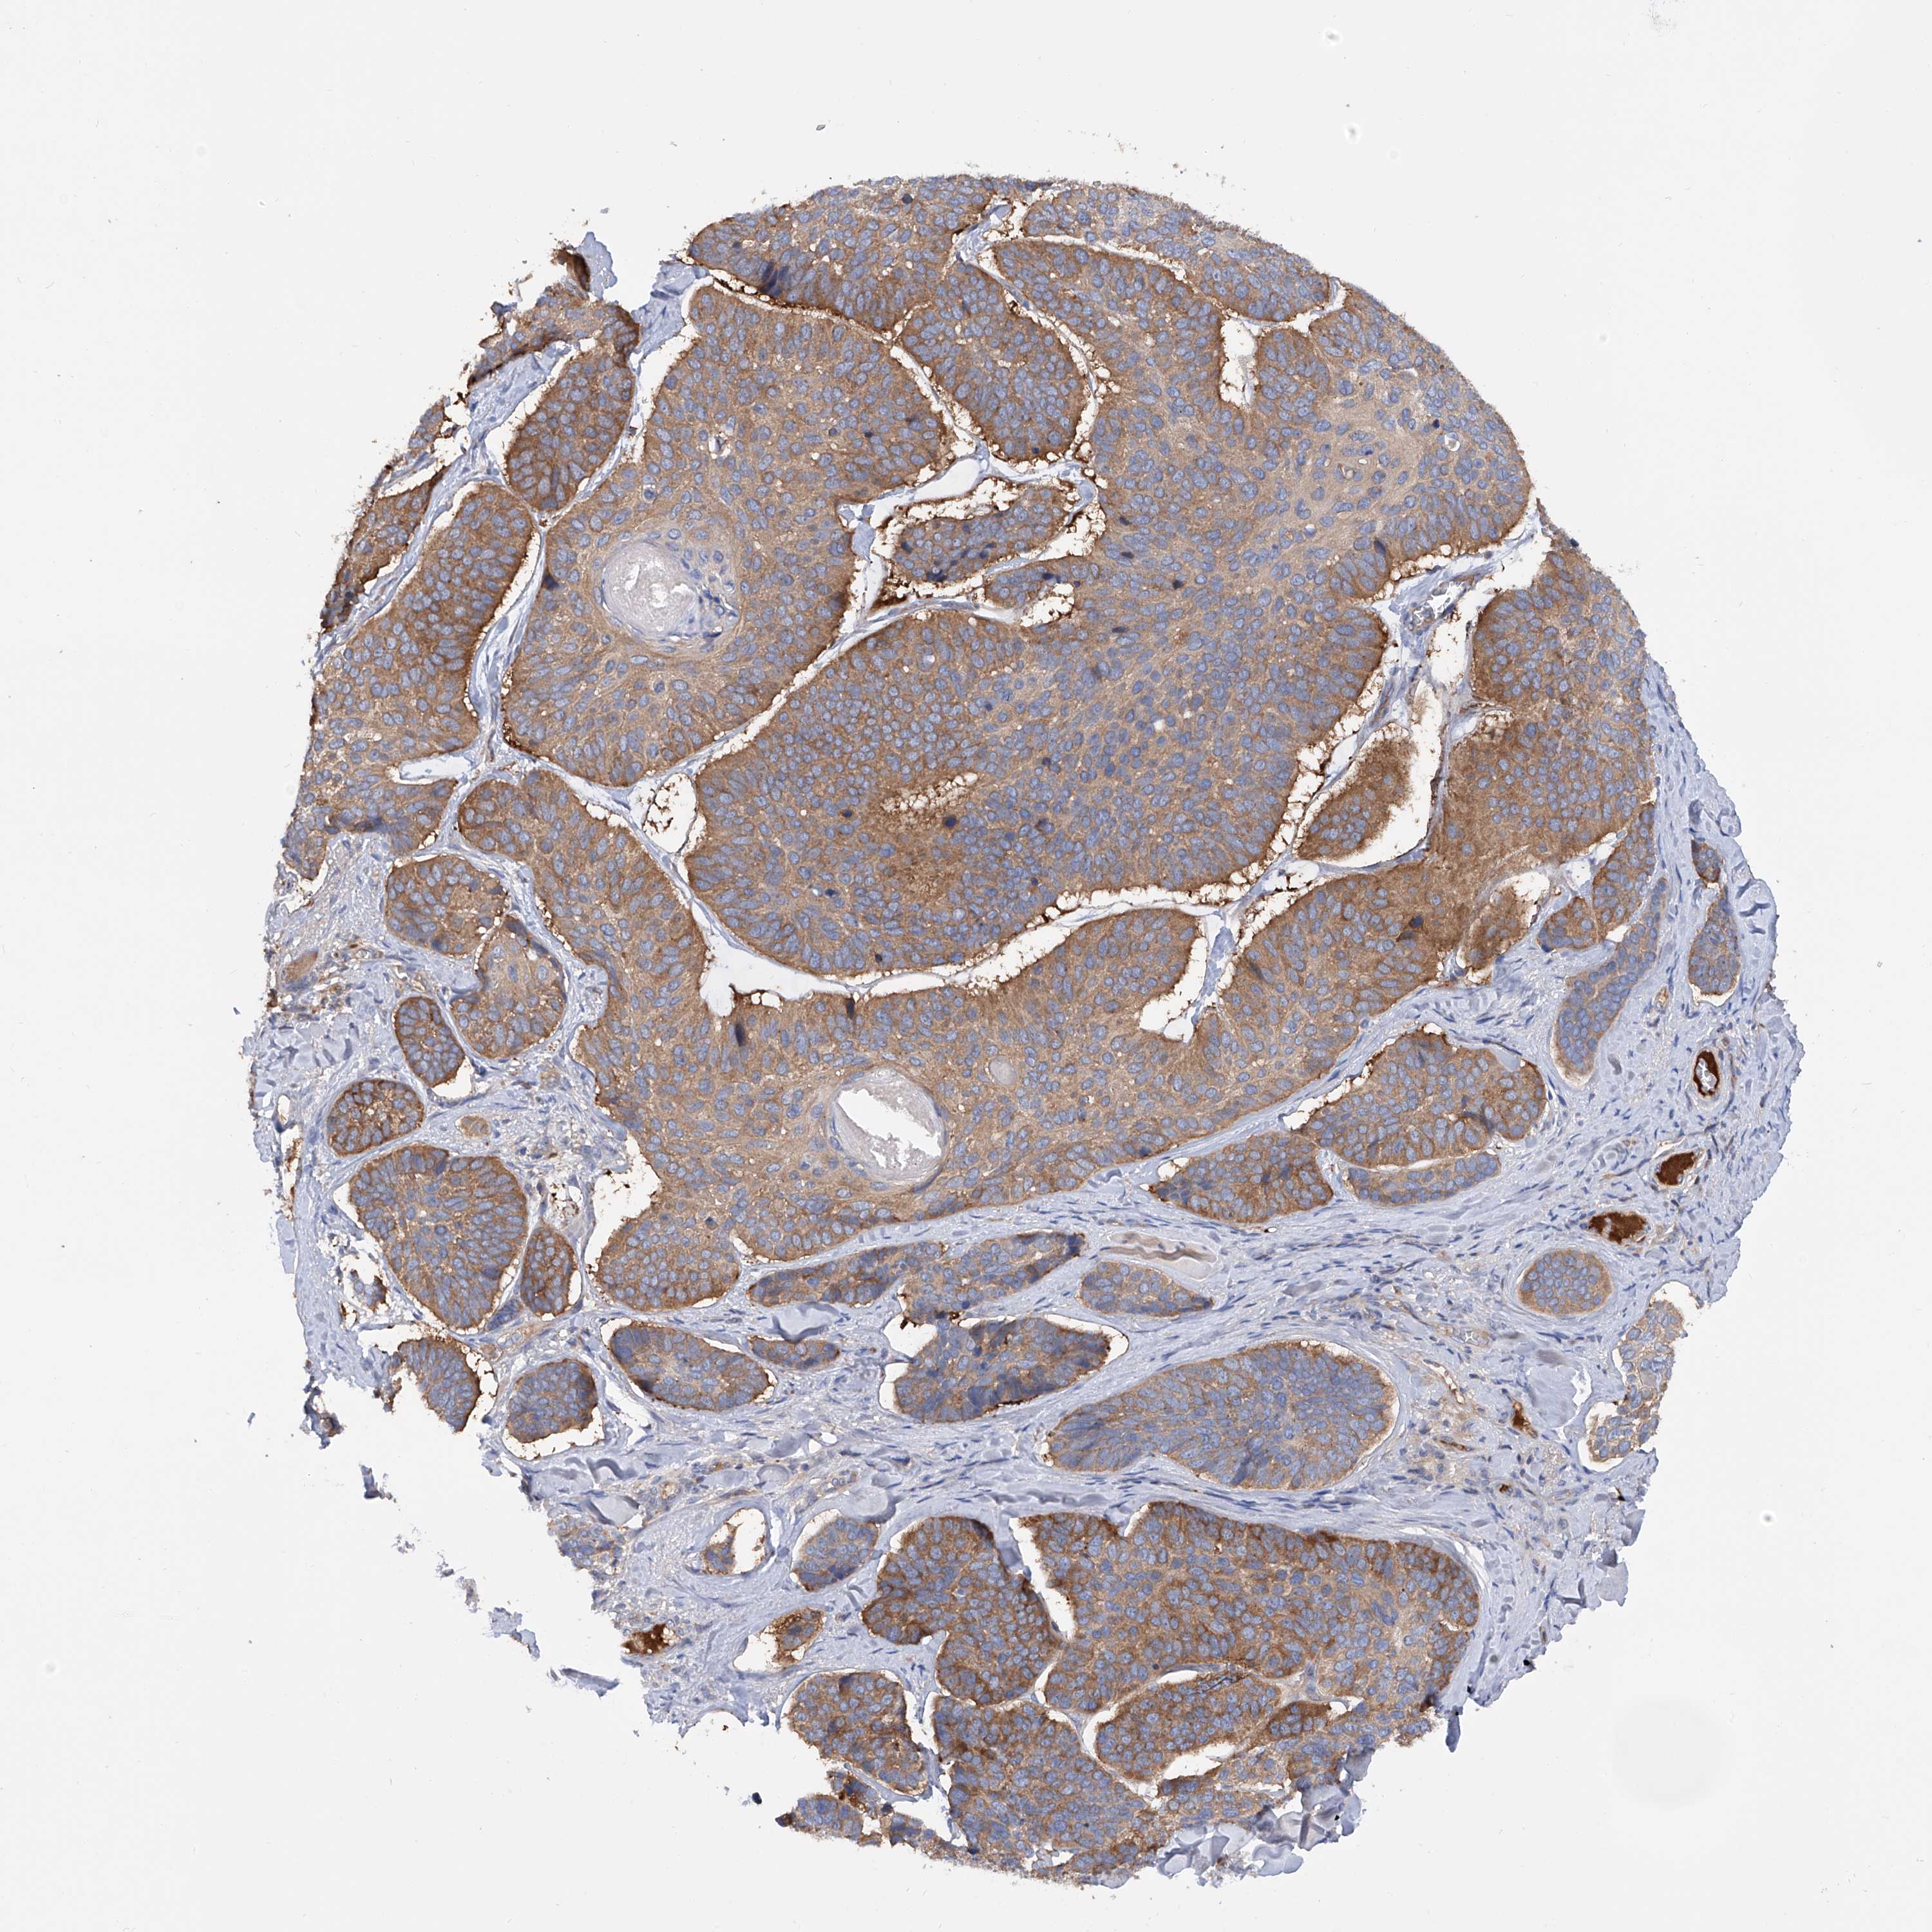

Basal cell and squamous cell cancer

SKIN CANCER - Protein expressioni

A mouse-over function shows sample information and annotation data. Click on an image to view it in a full screen mode. Samples can be filtered based on level of antibody staining by selecting one or several of the following categories: high, medium, low and not detected. The assay and annotation is described here.

Each image is clickable and will lead to virtual microscopy that enables deeper exploration of all samples and also displays staining intensity scores, fraction scores and subcellular localization as well as patient and tissue information for each sample.

Antibody HPA030145

Staining

High

Strong

>75%

Location

Cytoplasmic/membranous

Basal cell carcinoma